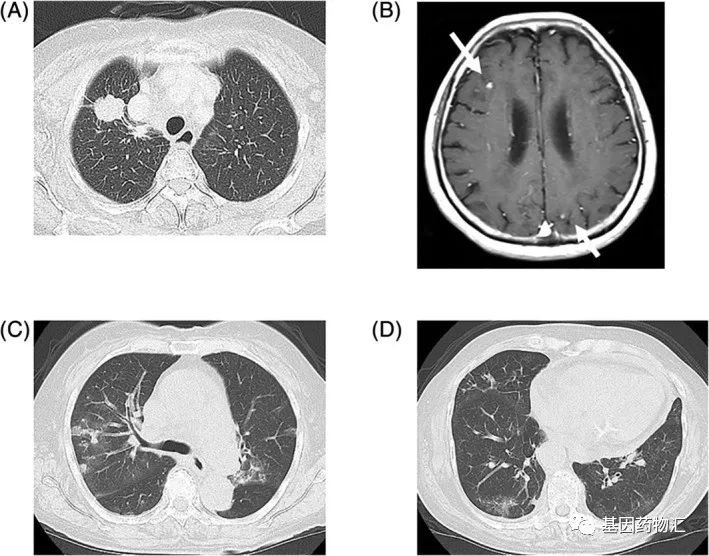

患者高龄,85岁,女性,为ROS1重排的肺腺癌患者。确诊时患者存在多处脑转移,分期为ⅣB期。

作为一线方案,患者接受了克唑替尼的治疗。疗效很快展现。治疗33天时,患者的原发病灶出现了部分缓解;治疗38天时,在没有接受任何颅脑放疗的情况下,患者的脑转移病灶达到了完全缓解。

但伴随着较好疗效的是严重的不良反应。患者从第8天开始恶心呕吐,至第57天这种不良反应变得难以忍受,患者的用药剂量降低到最初的一半。至第115天,胸部CT检查发现患者因药物治疗出现了间质性肺病。

尽管此时肿瘤病灶的控制仍然良好,处于部分缓解的标准,但患者不得不引入了激素治疗,并且停用克唑替尼。

考虑到患者还没有发生耐药突变,医生做出了决断——继续为患者使用第一代的ROS1抑制剂,从克唑替尼改为恩曲替尼!

用药28天,患者的病灶持续缩小;至用药6个月以后,患者仍在持续接受治疗,期间没有发生任何的不良事件。